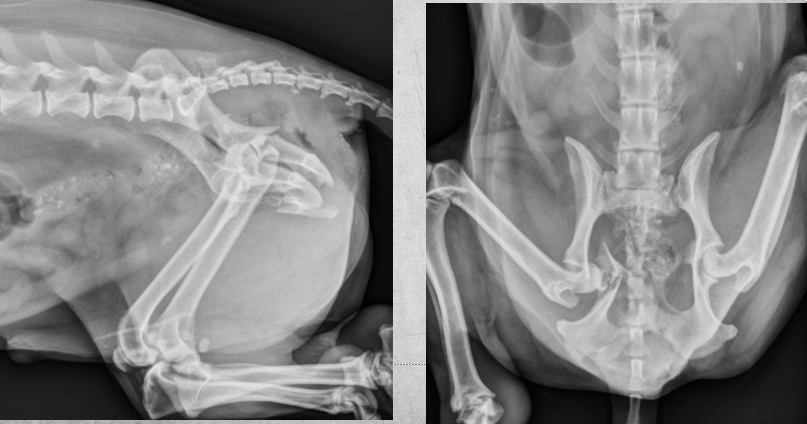

Q

2 years old male castrated cat

Severe sudden onset lameness of pelvic limb

Displaced capital physeal fracture of the left femoral head with mild cranial displacement of the femoral neck. On the frog-legged VD projections, this displacement is not visualizing so well.

Most of the physes of the pelvic limbs are at least partially open, including the intact right femoral capital physis (castrated young).

Diagnosis: Left sided capital physeal fracture of the left pelvic limb and delayed physeal closure in both hind limbs.